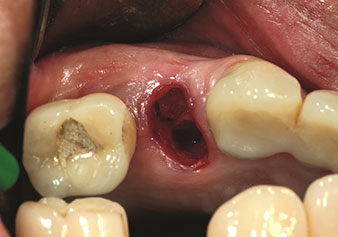

Sıklıkla hafife alınan uygulamalardan biri, alveolar yönetimin bir parçası olarak diş köklerinin veya kök parçalarının nazikçe çıkarılmasıdır. Şu anda iki modeli (W&H'ten EX1 ve EX2) mevcut olan hassas periotomlarla, özel olarak endodontik ön işleme tabi tutulmuş dişler veya ankilozik kökler de kolayca çıkarılabilir. Sonuç, sert ve yumuşak dokuları tamamen sağlam olan ekstraksiyon alveolleridir, çünkü genellikle onları açmak gerekli değildir.

Bu, daha sonra veya hemen implant bakımı için optimum bir temel oluşturur [şekil 1 ve 2, Dr. Torsten Conrad’ın (Bingen a. Rhein) onayı ile kullanılmıştır].

Fotoğraf: © Dr Torsten Conrad (Bingen a. Rhein)